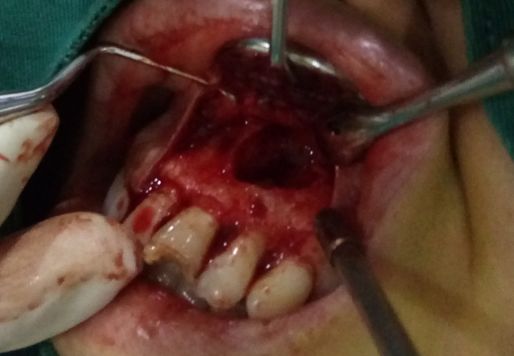

趙幫樹病例

來源于江思玉2群收集整理